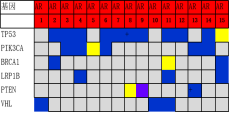

通过进一步基因表达谱测序���,对组织形态学和免疫组化水平界定的TNBC亚型的基因变异情况进行分析����,筛选各亚组之间的差异表达基因及表达意义探究��,结果显示���:1.免疫治疗相关的生物标记物MSI-H��、TMB-H����,作为一个低频发生事件����,在TNBC中不太可能常规作为免疫治疗有效性的评估手段��;TNBC的MSI发生机制可能与结直肠癌不同����、突变热点不同��。2. 整个研究队列中基因表达存在明显差异��,充分显示了患者个体间差异的存在����,从分子水平揭示了TNBC是一种高度异质性肿瘤��。3. TP53基因变异率发生最高��,提示在TNBC形成中可能扮演非常重要的角色����。4. TNBC分型的基因表达聚类分析方面存在差异(图2)����,这些差异基因参与了多种不同的生物学通路��,筛选特异的分子标记物或靶向治疗的靶点以期指导临床治疗���。

图2. 基于组织形态学及免疫组织化学标记物的TNBC亚型的基因表达聚类分析